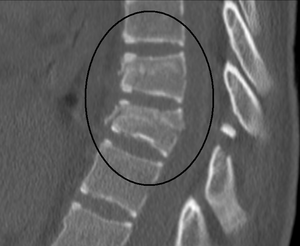

| A chance fracture of T10 and fracture of T9 due to a seatbelt during an MVC. | |

A Chance fracture is a flexion injury of the spine,[1] first described by G. Q. Chance in 1948.[2] It consists of a compression injury to the anterior portion of the vertebral body and a transverse fracture through the posterior elements of the vertebra and the posterior portion of the vertebral body. It is caused by violent forward flexion, causing distraction injury to the posterior elements.

The most common site at which Chance fractures occur is the thoracolumbar junction (T12-L2) and midlumbar region in pediatric population.[3] This fracture initially became known as a "seat belt injury" due to its association with the sudden forward flexion that occurs when one is involved in a head-on automobile collision while being restrained by a lap belt. With the advent of both lap and shoulder belts in the 1980s, Chance fractures have become less common especially now that lap-belt-only seat belts have been almost entirely phased out.